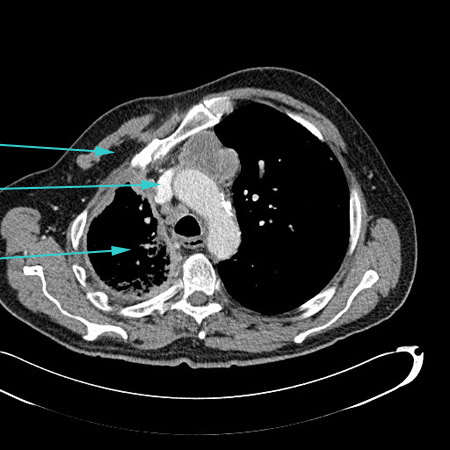

CT scan of chest showing empyema necessitans (long arrow), a chronic untreated empyema that has eroded through the thoracic cage and formed a subcutaneous abscess (short arrow)

From the collection of Dr Ami Rubinowitz; used with permission